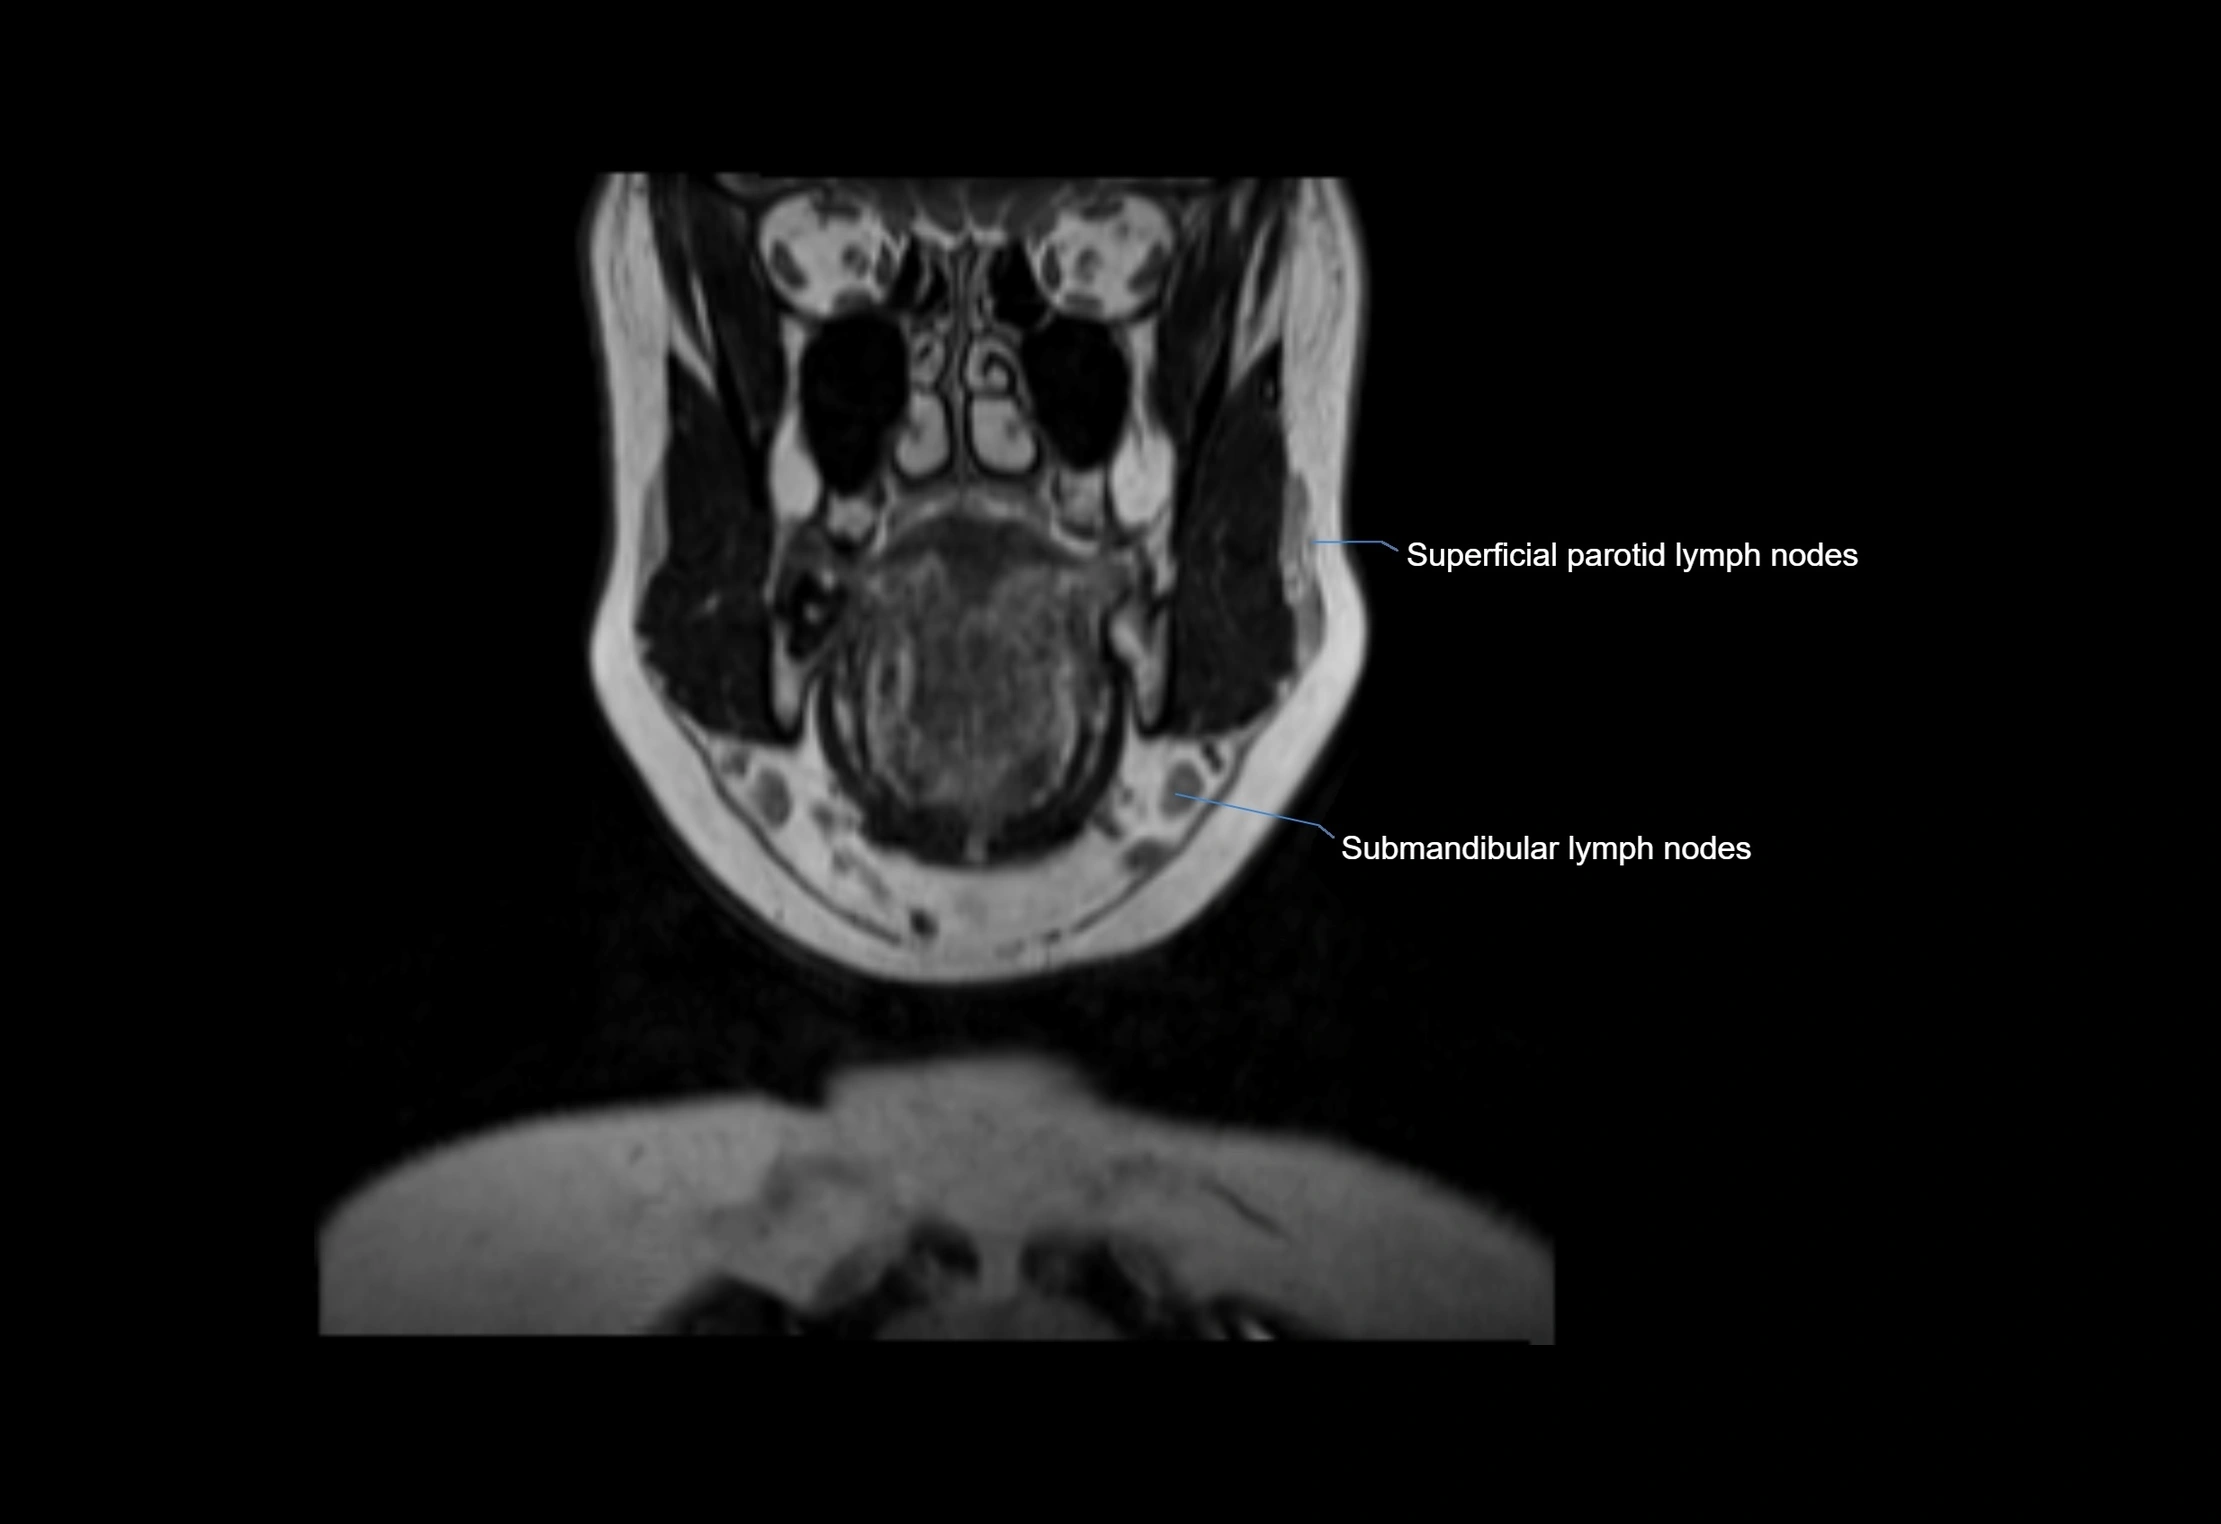

Location

• Found along primary lymph node chains, including preauricular, submandibular, parotid, and occipital regions

• Embedded in subcutaneous fat or superficial fascia, often lateral or posterior to primary nodes

MRI Appearance

T1-weighted images:

• Normal accessory nodes appear as small, oval hypointense to intermediate signal structures within subcutaneous fat

• Surrounded by hyperintense fat, enhancing contrast for visualization

• Pathological nodes may appear enlarged or rounded, sometimes with cortical thickening

MRI images

image